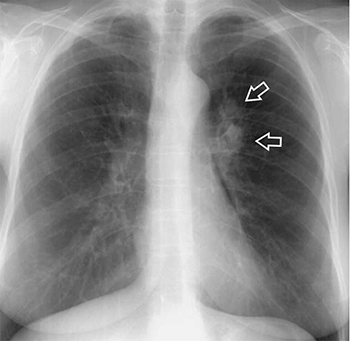

Диагностика плеврального выпота: что нужно знать